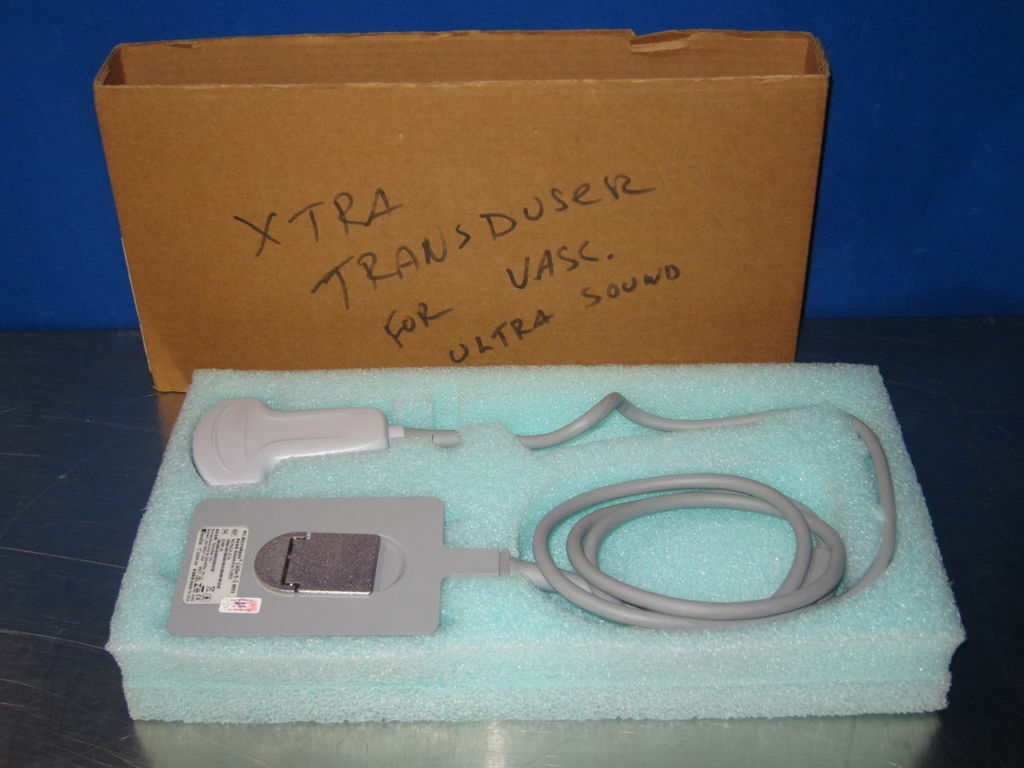

DIAGNOSTIC ULTRASOUND MACHINES FOR SALE

SONOSITE MicroMaxx Probe convex Transducer C60E

Sale price$ 1,638.36